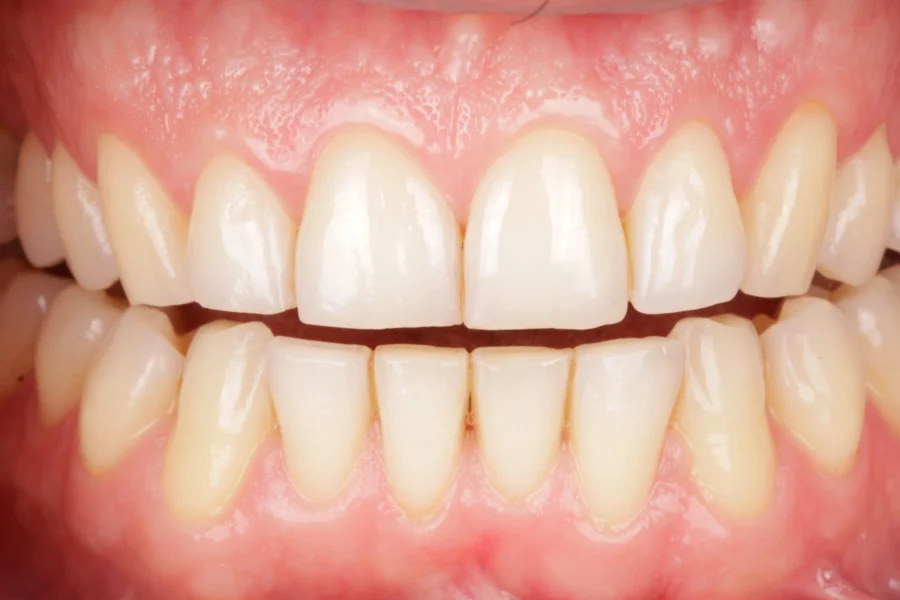

Cuanto mayor es el desgaste, mayor estructura dentaria hay que reponer, por lo que el tratamiento es más complejo, no porque sea complejo de ejecutar, si no porque cuanto más desgaste, mayor número de dientes estarán involucrados en el tratamiento. El material de elección suele ser la cerámica. Son tratamientos adhesivos, en los que utilizamos la estructura dental remanente para adherirnos a ella y devolver la anatomía perdida.

Apostamos por una estética dental que se percibe pero no se nota, aspirando siempre a conseguir unas restauraciones que se mimetizan y realzan la armonía natural de la sonrisa. El objetivo de las rehabilitaciones es equilibrar el aspecto de la sonrisa y devolver la funcionalidad.